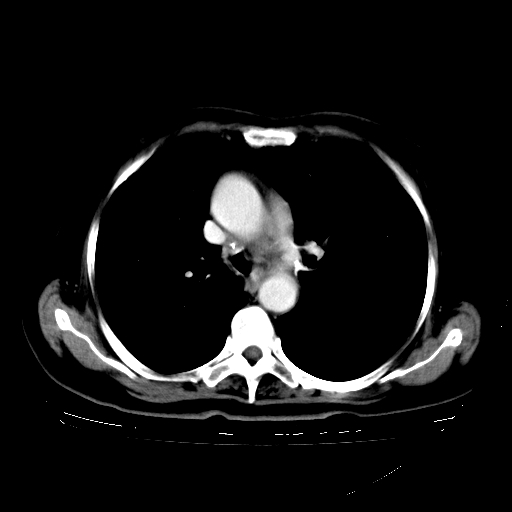

标题: CT23067:女,70岁,咳嗽、咳痰一个月,低热一周。 [打印本页]

女,70岁,咳嗽、咳痰一个月,低热一周。

1.左上肺结核,部分纤维化。右肺中下叶部分肺不张,内见液化、坏死及点状钙化,右中下叶支气管壁增厚、管腔狭窄,见多个点状钙化,结合临床考虑支气管内膜结核,建议痰检查抗酸杆菌并参考血沉。两肺多个小圆点状高密度灶,境界模糊,多考虑结核肺内播散。但本人年龄较大首先应支气管镜检以除外右肺癌。

2.胸主动脉夹层。

支持,首先一元论解释。胸主动脉部分层面环形低密度,中心强化。环形影不强化。不象真假腔的改变。我考虑动脉炎,不太支持夹层动脉瘤-和大家的观点不一致,希望楼主让患者再做个心血管的彩超吧。